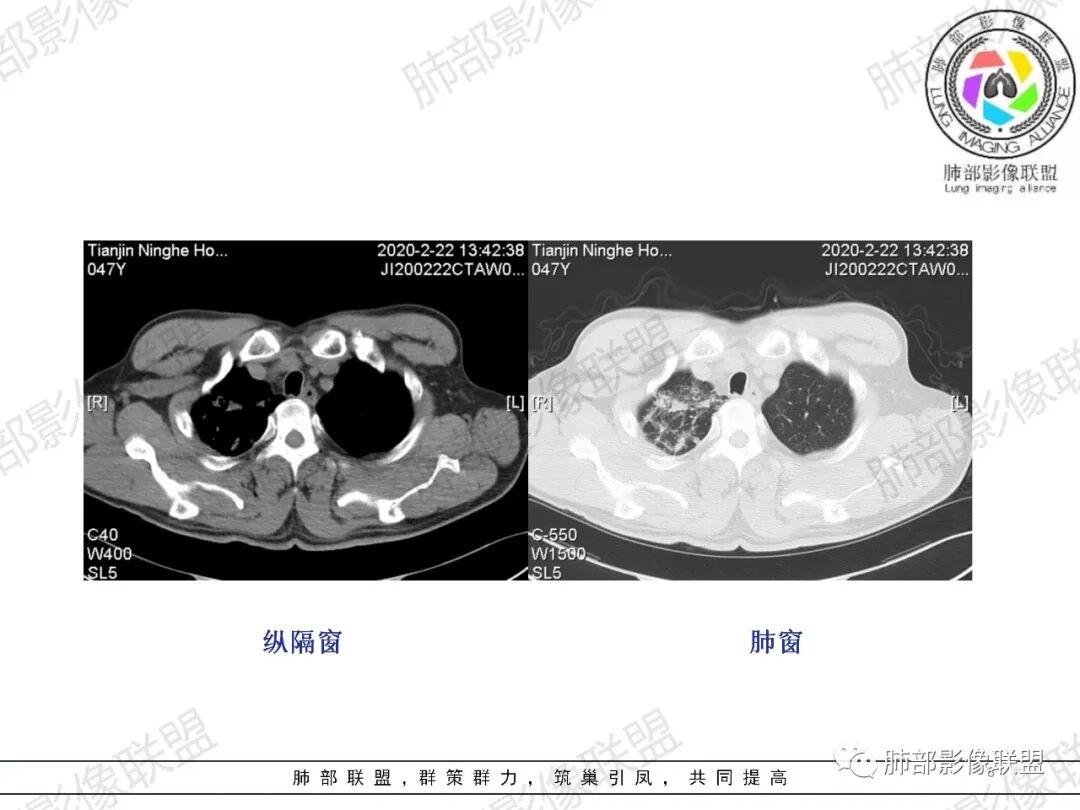

小兜:男,47岁,胸闷气短入院,一天前无明显诱因胸闷气短伴呼吸困难,夜间出现右侧胸痛,与呼吸及体位有关,曾有一次痰中带血。CT示右肺上叶尖段多发结节,条索影,可见树芽征及反晕征。右肺下叶胸膜下片状密度增高影,宽基底与胸膜相连,成扇形。综合考虑右肺上叶尖段结核可能;右肺下叶肺栓塞?病毒性肺炎?

水晶石头:患者中年男性,胸闷、气促1天。伴右胸痛及痰中带血。否认结核、心脏疾病等病史。查体无特殊。完善血常规白细胞计数、中性粒细胞百分比及C反应蛋白升高。心电图、B超、凝血功能、降钙素原、脑钠肽正常。胸部CT:右肺上叶尖段多发结节、斑片、纤维条索影,见小叶间隔增厚及反晕征。右肺下叶后基底段胸膜下片状磨玻璃影,见小叶内间隔增厚。右侧胸膜增厚,未见明显淋巴结增大。综合考虑右上肺结核病变,右下肺肺栓塞。鉴别病毒性肺炎及恶性病变。

右上叶,多灶性、多态性,烟花征,结核应该没问题

然后就是右下叶病灶的问题

后基底段,胸膜下,这个没问题吧

我们看看病变的形态、密度、边缘、内部改变

GGO密度

边缘不清

可惜没有重建,楔形?

细网格明显

支气管通畅,壁增厚

血管增粗